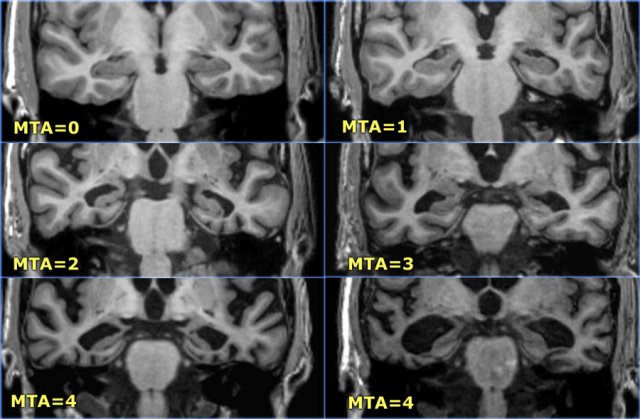

MTA-scale for Medial Temporal lobe Atrophy

The MTA-score should be rated on coronal T1-weighted images at a consistent slice position.

Select a slice through the corpus of the hippocampus, at the level of the anterior pons.

> 75 years : MTA-score 3 or more is abnormal (i.e. 2 can still be normal at this age)

Data from a study with 222 controls and patients with various forms of dementia in which this visual rating scale was used to assess temporal lobe atrophy suggest that sensitivities and specificities of 85% can be obtained for patients with AD.

The score is based on a visual rating of the width of the choroid fissure, the width of the temporal horn, and the height of the hippocampal formation.

• score 0: no atrophy

• score 1: only widening of choroid fissure

• score 2: also widening of temporal horn of lateral ventricle

• score 3: moderate loss of hippocampal volume (decrease in height)

• score 4: severe volume loss of hippocampus

< 75 years: score 2 or more is abnormal.

> 75 years: score 3 or more is abnormal.

Scroll through the images

Here you can scroll through the images for examples of MTA score 0-4.